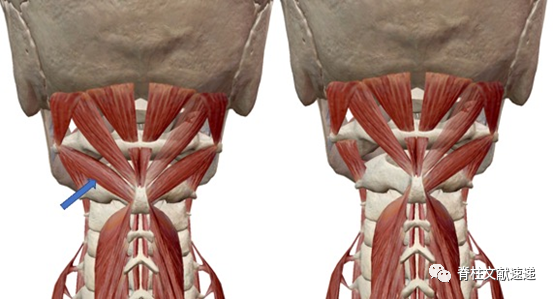

2)颈部肌肉情况,如下图所示,寰枢椎固定手术涉及的肌肉主要有头后大直肌、头后小直肌、头下斜肌、多裂肌、颈半棘肌和颈棘间肌。头下斜肌连接C1横突和C2棘突,遮挡C1/2侧块关节,是必须牺牲的。而头后大直肌可部分保留,头后小直肌、多裂肌、颈半棘肌和颈棘间肌可基本完全保留,很大程度的保留了枕下肌群。而常规切开寰枢椎固定上述肌肉均需切断。

上图:左侧为枕下肌群,箭头所指为头下斜肌;右图中为切除头下斜肌后显露C1/2侧块关节。